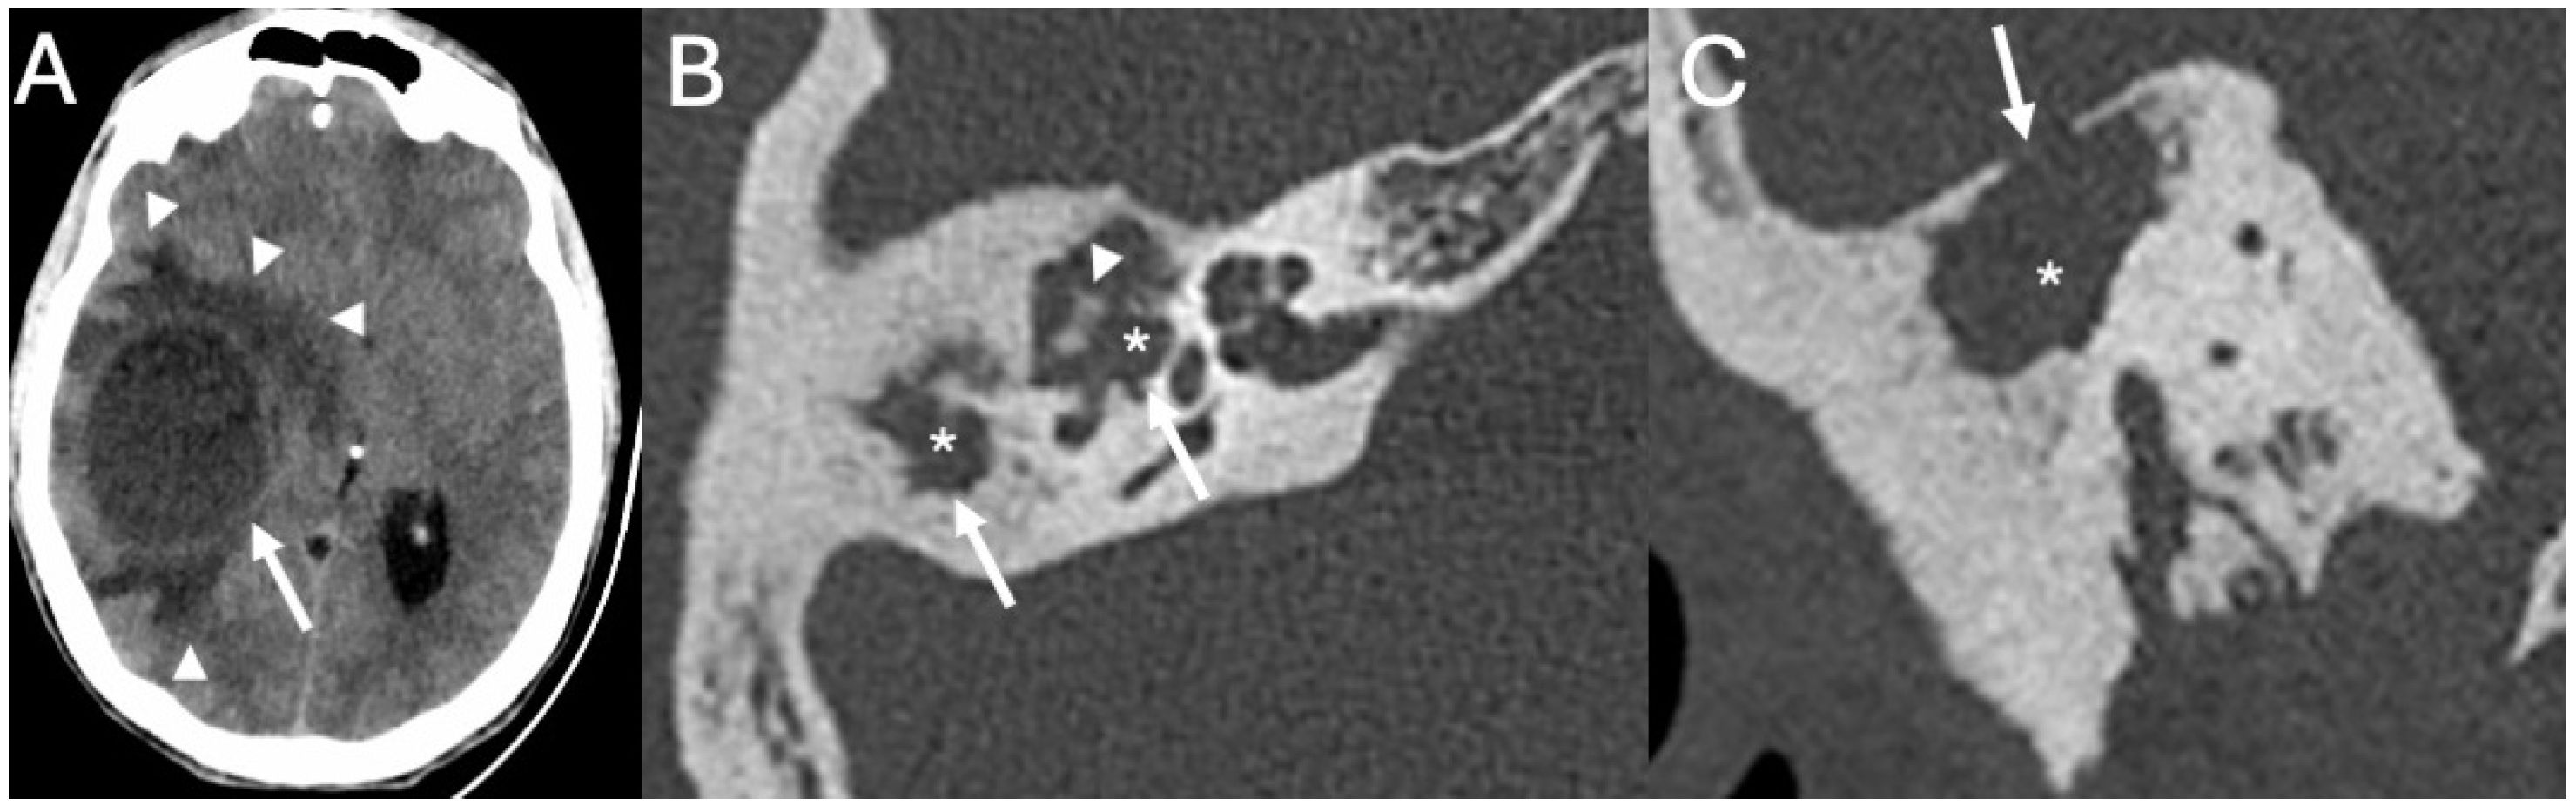

3.3. Cholesteatoma

3.3.1. Imaging

3.3.2. Complications

| Cholesteatoma and Otogenic Complications | Kuo et al., 2015 [26]; Baráth et al., 2011 [27]; Mustafa et al., 2014 [28]; Dubey et al., 2010 [29]; Sun et al., 2014 [30]; Lee et al., 2020 [31] | Reviews and retrospective studies | Cholesteatoma causes erosion and CSF leak, leading to meningitis (12–30% incidence); MRI improves detection; pediatric risk emphasized. |